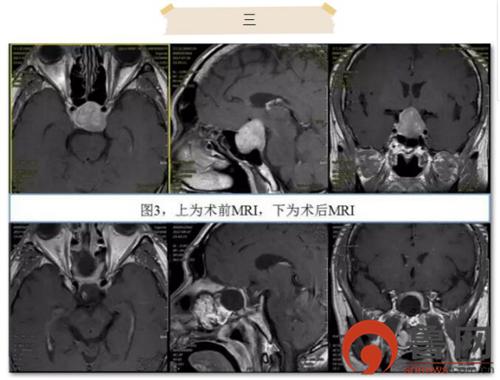

患者3为59岁男性,因视力视野障碍、全身乏力入院。术前MRI检查显示鞍区占位,考虑为垂体瘤。经历过上两例的复杂手术,该患者的手术显得“小菜一碟”。制作粘膜瓣、暴露蝶窦、扩大蝶鞍、鞍内切除,修补鞍底……手术一气呵成,仅用时1小时,出血不足50ml,患者术后5天即康复出院,未出现任何手术并发症。复查MRI显示肿瘤全切(图3)。